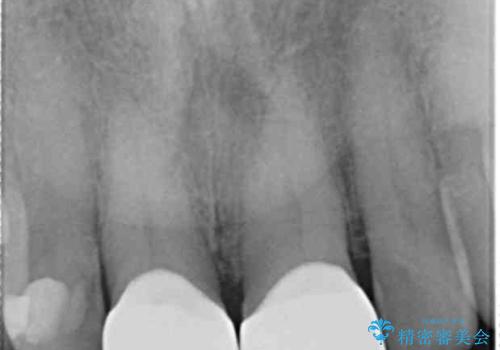

- 前歯の小さな虫歯を複数回治療した結果、つぎはぎだらけになってしまい審美的な改善を求めて来院されました。

これ以上のコンポジットレジン修復は更なる審美障害を招きかねないので、全体を覆うセラミッククラウンを選択します。

ディープバイト・噛み合わせが強いことからフルジルコニアクラウンを選択しました。